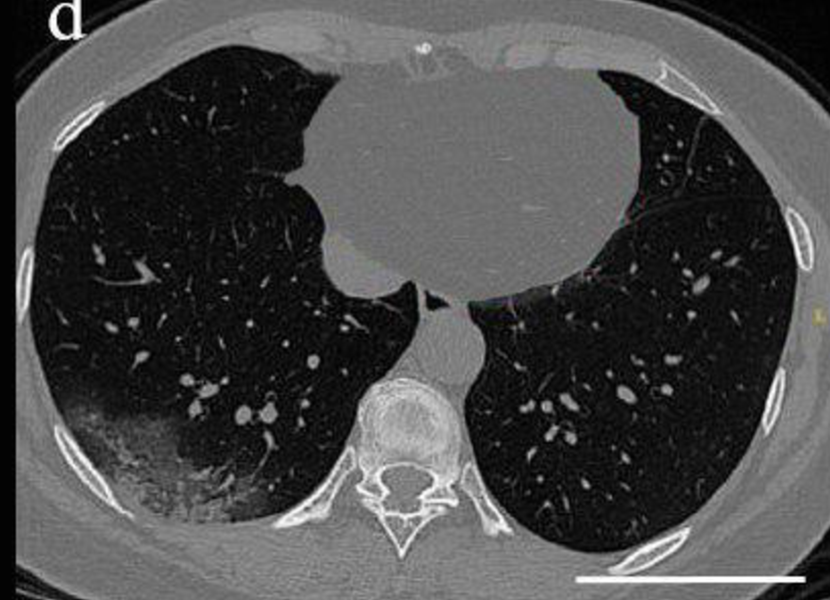

CT dataset has 349 Covid images and 397 non-Covid images [37]. Health professionals prefer breast CT scans as they carry more information compared to chest X-rays to use for medical diagnosis. Fig. 3 shows both a Covid and a non-Covid case from the CT database.

Refer to caption

(a) Covid

(b) Normal

Figure 3: Two sample images from CT dataset.